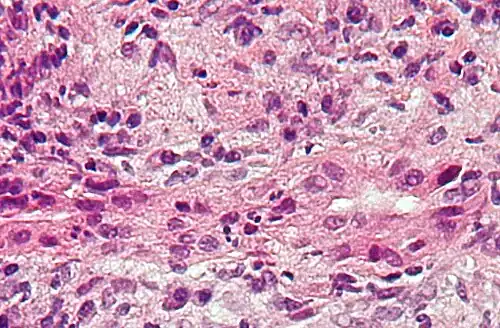

Mikrofoto einer Leberbiopsie bei Primär biliärer Zirrhose mit Inflammation der Gallengänge. (HE-Färbung).

Eine Leberpunktion (Leberbiopsie) kann bei der Erstdiagnose helfen, die Diagnose auch über eine Gewebeuntersuchung abzusichern.